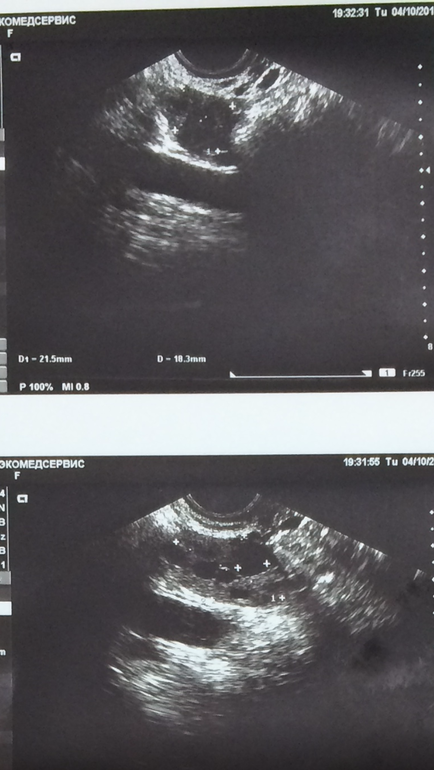

Верхнее фото какого яичника? Не могли бы увеличить? Киста - это образование от 30мм, поэтому перепутать сложно. Фолликул вырастает максимум до 25-26мм.

Теперь вижу. Я бы не говорила о мелкокистозной структуре, но левый яичник имеет кистозную трансформацию, то есть видны только фолликулы, при отсутствии достаточного количества ткани яичника. Если врач говорит о кисте 9мм, то это никак не функциональная киста. Это либо фолликул, либо, если врач считает, что это не фолликул точно, то должен предположить кисту параовариальную, к примеру, но не подходит ее распопложение, либо эндометриоидную, но строение иное, либо должен сказать о кисте в стадии регресса, но для этого он должен знать, что на этом самом месте ранее была киста больших размеров.

И в заключении написали что функциональные кисты до 9 мм, а везде указано что кисты должны быть больше